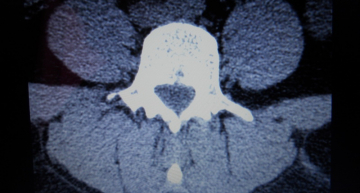

Здравствуйте, меня зовут Наталья, мне 35 лет. С 20 лет у меня болела спина, а 2 года назад боли почти прекратились, но стали млеть руки и ноги.    После обращения к невропатологу предварительный диагноз врач поставил демиелинизирующее заболевание ЦНС. Было сделано МРТ головы и шеи. Демиелинизирующее заболевание ЦНС не подтвердилось, а обнаружилось: Межпозвонковый остеохондроз шейного отдела позвоночника, осложненный медианной протрузией диска С6-С7.    Пройдено лечение лекарствами. Состояние ухудшилось: мление рук и ног уменьшилось, а головокружение и боли в голове, а так же в спине увеличились. Резко стало бросать то в жар, то в холод, при условии, что признаков ОРЗ нет.   При повторном обследовании МРТ шейного, грудного и пояснично-крестцового отдела позвоночника мне выдали протокол исследования. Печатаю дословно....   При исследовании шейного, грудного и поясничного отдела позвоночника костно-деструктивных изменений не обнаружено. Отмечается снижение сигнала и высота м/п дисков, сглаженность шейного и поясничного лордоза, субхондральный склероз замыкательных пластин, признаки начальных артрозных разрастаний в м/п суставах, грыжи Шморля Т7-12. Отмечаются:   - протрузии дисков С4-5, С5-6, С6-7 до 2,5 мм с сужением СМК до 11 мм, нерезкой компрессией переднего арахноидального пространства, нерезким сужением м/п отверстий   - медианная грыжа диска Т6-7 до 3 мм сужением СМК до 14,5 мм, компрессией переднего арахноидального пространства   - протрузии дисков Т7-8, Т8-9 до 1,5 мм с нерезкой компрессией переднего СА пространства   - протрузии дисков L4-5   L5-S1 до 2,7 мм с сужением СМК до 16 мм, дурального мешка до 11 мм с нерезкой его компрессией, нерезким сужением входа в м/п отверстия   В теле Т6 определяется гиперинтенсивный в обоих режимах очаг размерами 8*9 мм, аналогичный очаг определяется в теле L3 размерами 5*6 мм   Сагиттальный ПК на уровне тел позвонков С4-5 до 13,5 мм (сужен), Т5-6 до 15 мм,  L4-5 до 15,5 мм   Релаксационные характеристики и конфигурация спинного мозга не изменены.   Пре и паравертебральные ткани не изменены.   Сигнальные характеристики крестца, копчика и подвздошно-крестцовых сочленений не изменены.   ЗАКЛЮЧЕНИЕ: МРТ признаки дегенеративно-дистрофических изменений позвоночника ( остеохондроз, спондилоартроз, грыжи Шморля), протрузии выше указанных м/п дисков, грыжа диска Т6-7, Гемангиомы Т6, L3.   Подскажите пожалуйста, как быть и что делать????  Заранее спасибо.

Добрый день! Гемангиомы позвонков - это доброкачественные образования, которые встречаются у 5-10% здоровых людей. Делать с ними ничего не нужно, только наблюдать в динамике. Дегенеративно-дистрофические заболевания позвоночника лечатся у невролога, симптоматика у них самая разнообразная (это и головокружение и головные боли и прочее). Нередко в таких ситуациях дополнительно назначают УЗИ сосудов шеи, выполняют МР-ангиографию шеи. Можно выполнить КТ-исследование шеи с болюсным усилением для исключения аномалий и патологии вертебробазилярной области. Судя по данному заключению МРТ, ничего страшного в позвоночнике не обнаружено. Грыжа межпозвонкового диска иногда требует нейрохирургического вмешательства.